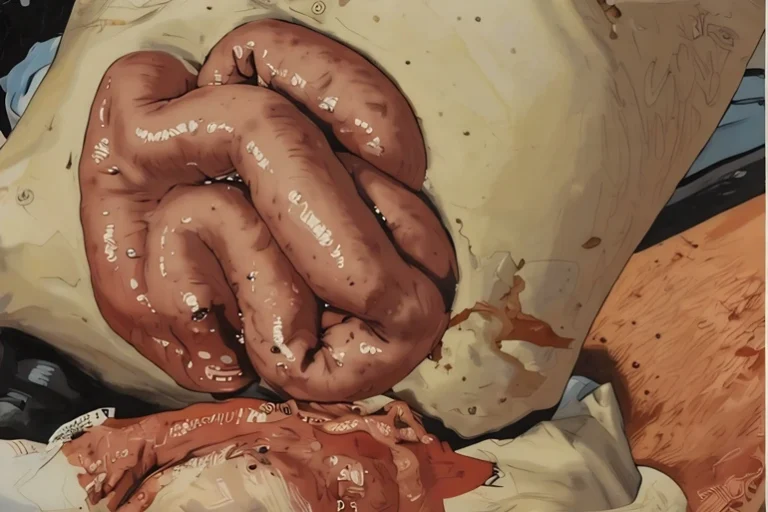

→Image at top is an artistic rendering from a 14-year-old boy who sustained a penetrating injury to his abdominal wall after impacting the handlebars of his bike. Note the bowel perforation at approximately 7 o’clock on the bowel. This should not be reduced, as it will spill bowel contents into his abdomen. 5

If there is a rupture or leakage of the bowel contents, no attempt should be made to reduce the evisceration as that would just spill bowel contents into the abdomen, all but ensuring significant intra-abdominal infection. Similarly, if any associated bowel bleeding can’t be controlled, that too is a contraindication to reduction.4